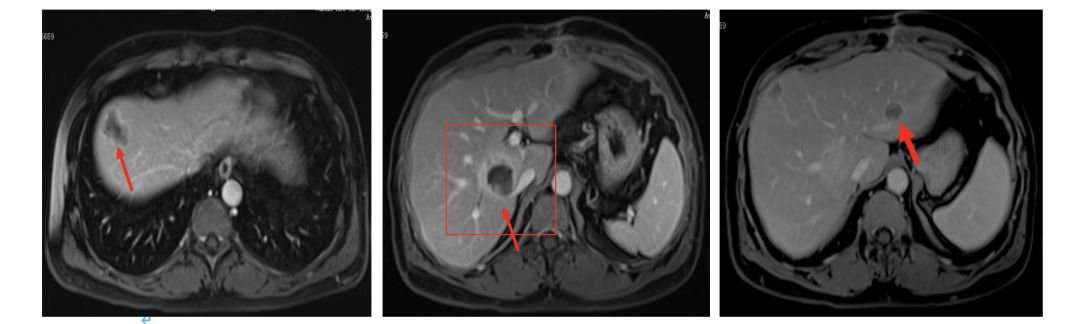

2017.6复查肝脏再次出现新病灶,右后叶包膜下边缘见2.2cm*1.4cm强化结节。

MDT讨论意见

肝脏病灶单发;

肝脏病灶争取局部治疗达到NED;

建议行肝脏转移灶手术治疗;

肝脏病灶手术治疗。

2017.6.6行腹腔粘连松解术+肝转移瘤切除术;

术后病理(肝右叶)绒毛管状腺癌,结合临床病史,符合结肠癌肝转移。

2017.7行肝转移灶术后瘤床放疗DT36Gy/6F;

唯一我有点疑问,为什么这次手术时,我们从片子上可以看到,是个比较靠近肝脏边缘的病灶,应该是很容易达到R0切除,很容易达到一个满意切除的范围,不知道他们是出于怎样的考虑再次做了术后的放疗。是否觉得这次手术切除不满意?还是处于其他考虑。